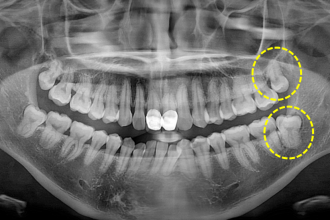

사랑니발치

굿프렌즈 치과 임상 케이스